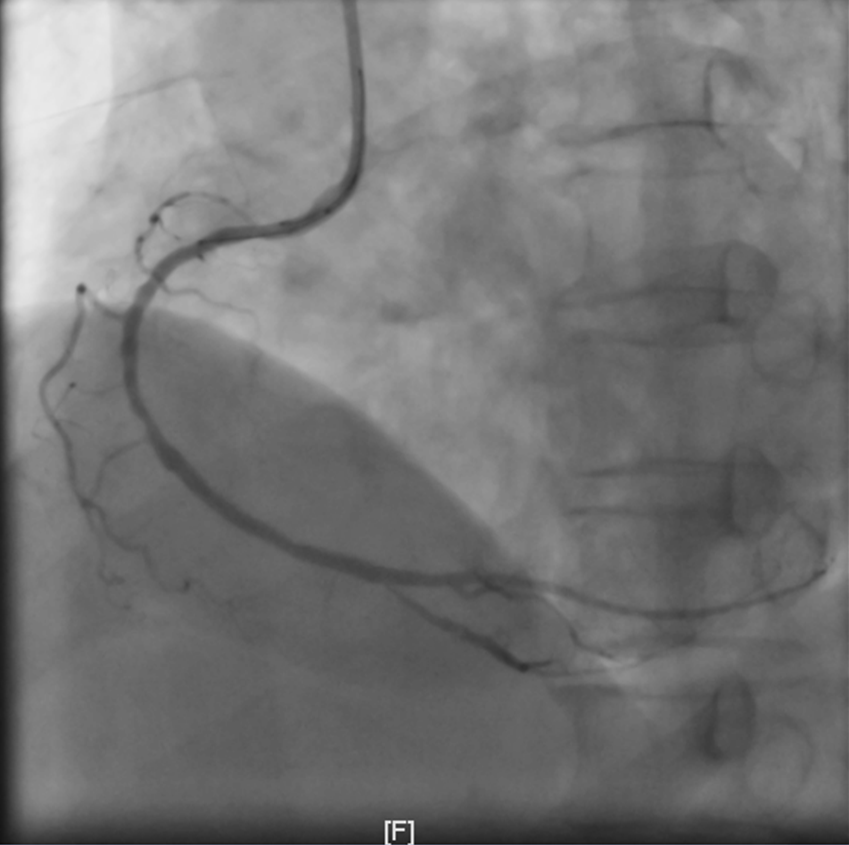

与余女士家属积极沟通后,余女士家属签署知情同意书,同时余女士在做好防护措施后立即送入介入室。在覃主任的带领下,陈志明副主任医师手术团队凭着娴熟的技术,仅用了33min开通患者罪犯血管—右冠中段闭塞血管,成功挽救了余女士的生命。术后余女士送入心血管内科CCU继续治疗,目前已康复出院。

血管打通